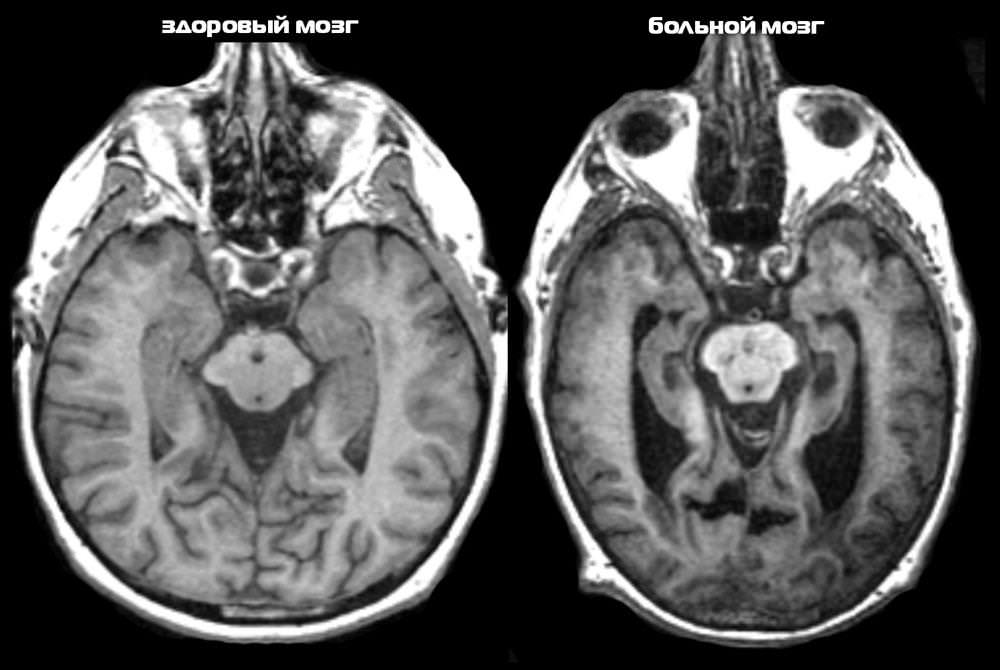

Что такое цирроз? Эта болезнь проявляется у больных алкоголизмом людей, которые постоянно принимают алкоголь. В этом случае ацетальдегид не успевает расщепляться до уксусной кислоты, с каждым приемом уничтожается все больше и больше клеток печени, в результате чего она перестает функционировать и отмирает.